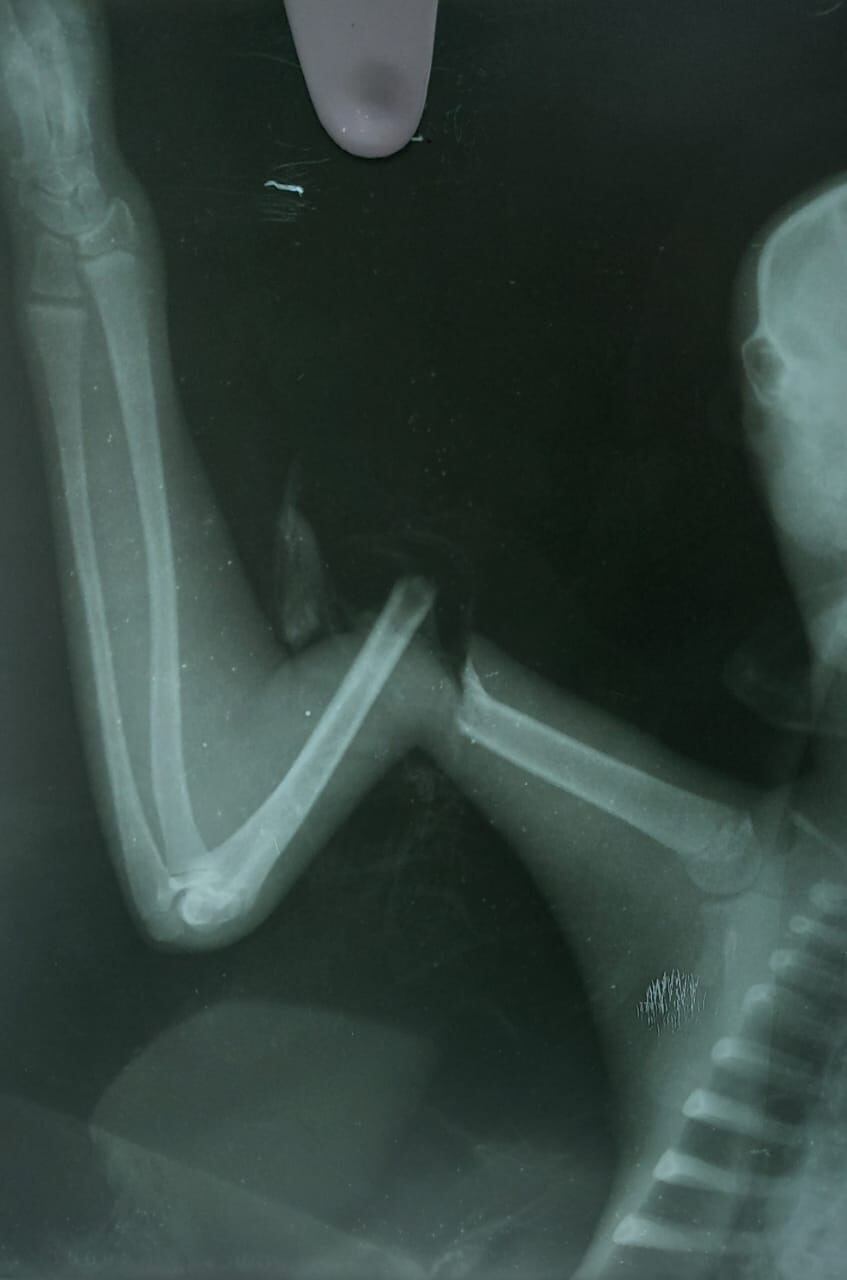

Dos perezosos fueron rescatados por la CAS, uno mutilado 3 dedos de su pie der a consecuencia de disparos de perdigones en la #Belleza y otro en #Cimitarra con una fractura en su brazo derecho. Los dos ya recibieron atención médica y se encuentran en proceso de rehabilitación pic.twitter.com/ucOu8EB9Si

El otro caso correspondió a un perezoso de edad adulta, que fue rescatado en el municipio de Cimitarra con una fractura, con herida abierta en una de sus extremidades. Este espécimen fue trasladado a Barrancabermeja para ser intervenido en la Clínica Misión Médica, en donde luego de una cuidadosa y minuciosa cirugía, los especialistas lograron salvarle la vida.